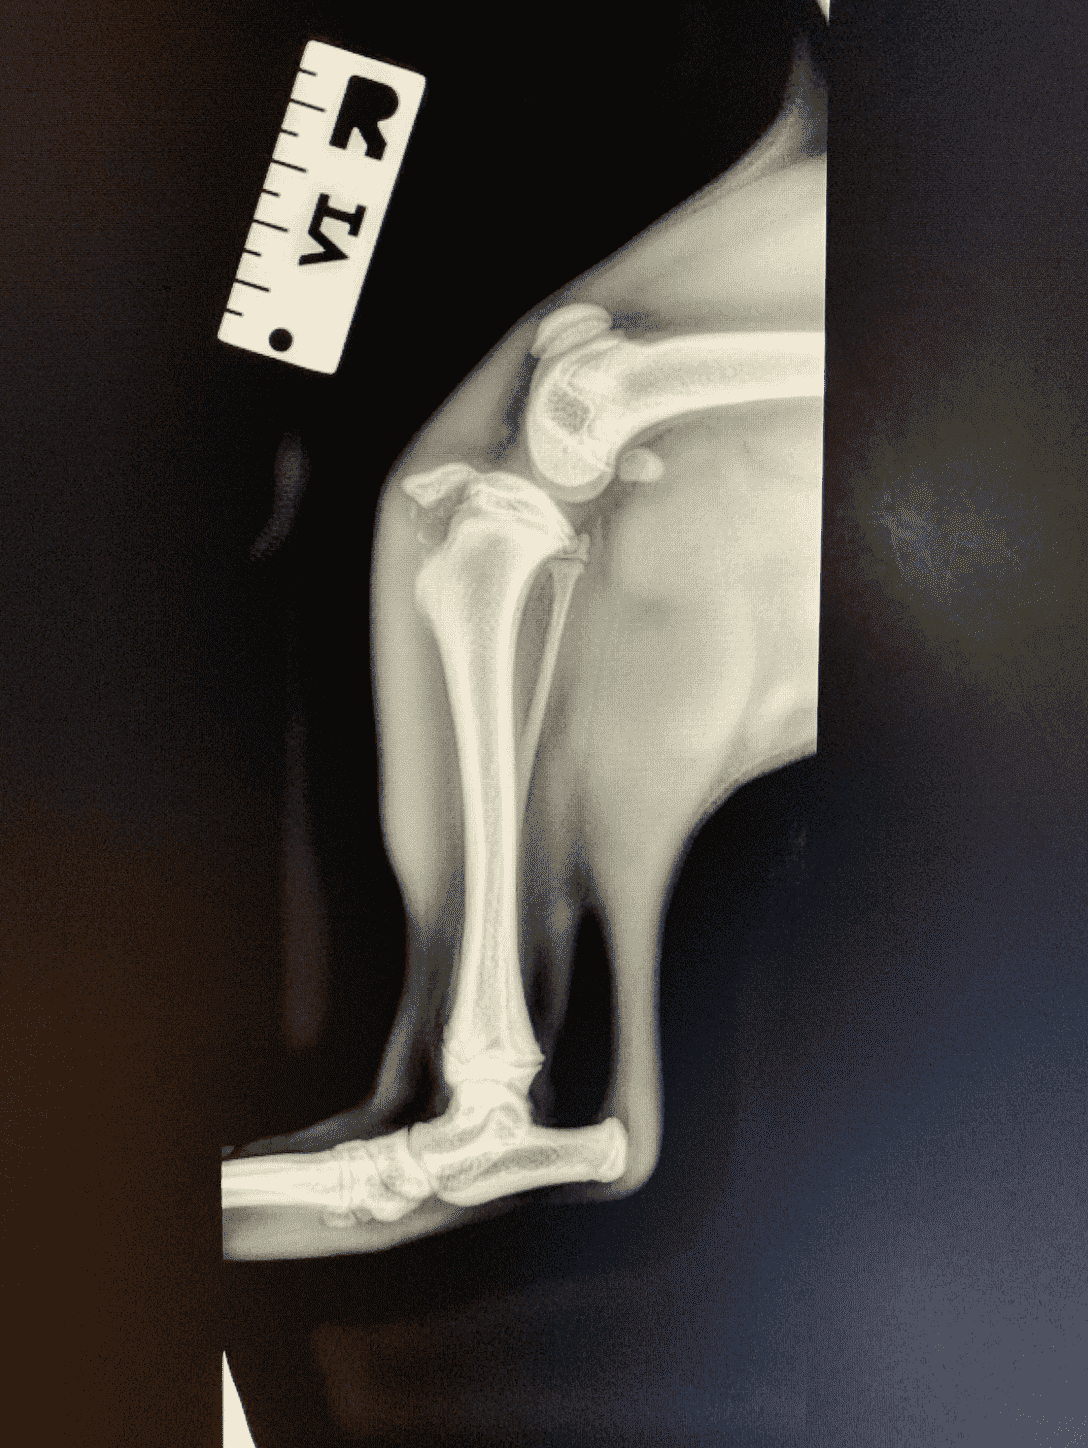

A young French Bulldog puppy named Fred presented to our clinic with a history of sudden right hindlimb lameness (limping). The owners didn’t see any major trauma, but they think he might have tried to jump up onto the bed and missed.

When examining the puppy, his right stifle (knee) was painful and swollen. The next steps included x-rays to investigate the limping.

We performed x-rays which revealed the puppy had fractured his tibia (bone in the leg). The specific fracture area was the tibial crest, which is prone to fracturing in young dogs if they hurt their stifle. See the x-rays attached, right and left stifle, for comparison.